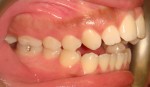

After Orthodontic Setup - Presurgical